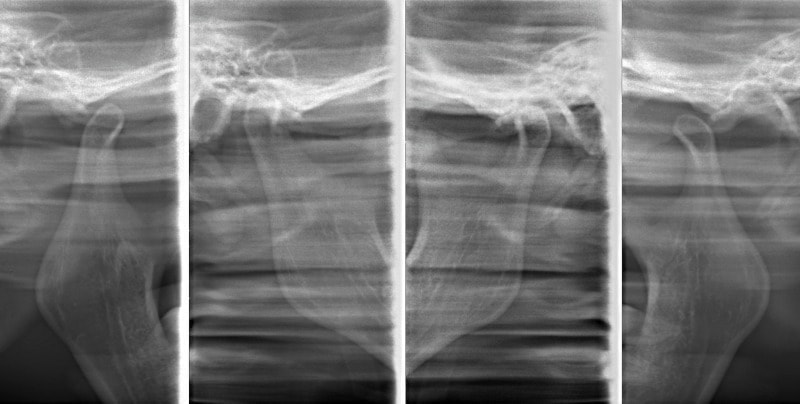

治療後顎関節レントゲン

CO-CR位置の改善が認められます。